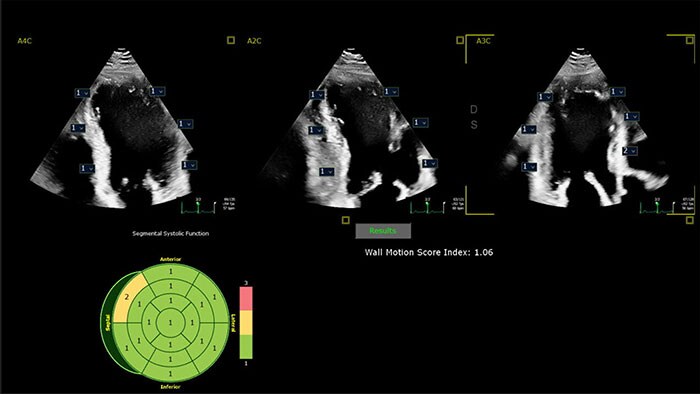

Cardiovascular Ultrasound

Intuitive, reproducible, AI-enabled echocardiography

Powered by AI-based capabilities, our industry-leading CV ultrasound platform delivers advanced tools for structural heart disease, including 3D automated tricuspid valve and color flow quantification tools. Efficient automation and quantification tools enable you to diagnose heart failure and coronary artery disease quickly and confidently. Tiny transducers, high frame rates and sharp imaging support confidence in pediatric echo exams. Unified on- and off-cart workflow supports lab setup and consistent UI and workflow across systems.

Philips AI-based ultrasound solutions integrate into everyday clinical workflows and are designed to make it easier and faster for clinicians to acquire, select, measure and report accurate results.